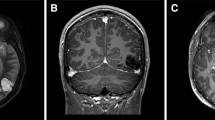

AA is an 81-year-old right-handed housewife with 8 years of education, who was hospitalized for a stroke involving the left occipital and temporo-occipital inferior and mesial cortical and subcortical structures, due to occlusion of the left posterior cerebral artery. Ten days after the event, she was hospitalized to take part in a neurorehabilitation program: at a first neurological examination, she presented with mild right hemiparesis; Humphrey’s visual field perimetry revealed right homonymous hemianopia, which was acknowledged but not completely compensated by the patient (Fig. 3). A clinical neuropsychological assessment revealed the presence of alexia without agraphia (see Bonandrini et al. 2020; for a detailed description of the reading impairment) and naming deficits limited to the visual modality. The Aachen Aphasia Test (AAT, Huber et al. 1984; Luzzatti et al., 2023, 2024) revealed that spontaneous speech was only mildly impaired, showing very slight difficulties in lexical access (score 4/5), with no additional phonological, morphosyntactic or articulatory and prosodic impairment. Reading aloud was severely impaired (1/30; Percentile Rank, PR: 13), as well as naming from visual presentation (moderate impairment: 55/120; PR: 38), producing, among other errors, several perseverations and verbal paraphasias (see Table 1).

(a) 3D rendering of the lesion after normalization to the standard MNI template; (b) 2D plot of the lesion at the level of the medial sagittal plane. Fluctuations in voxel intensity at the boundary of the lesion map are a byproduct of spatial normalization; (c) 3D rendering of the disconnectome map based on the patient’s lesion and structural connectivity estimates based on 100 healthy controls. For the original MRI scan see Bonandrini et al. (2020) (colors online and in PDF)